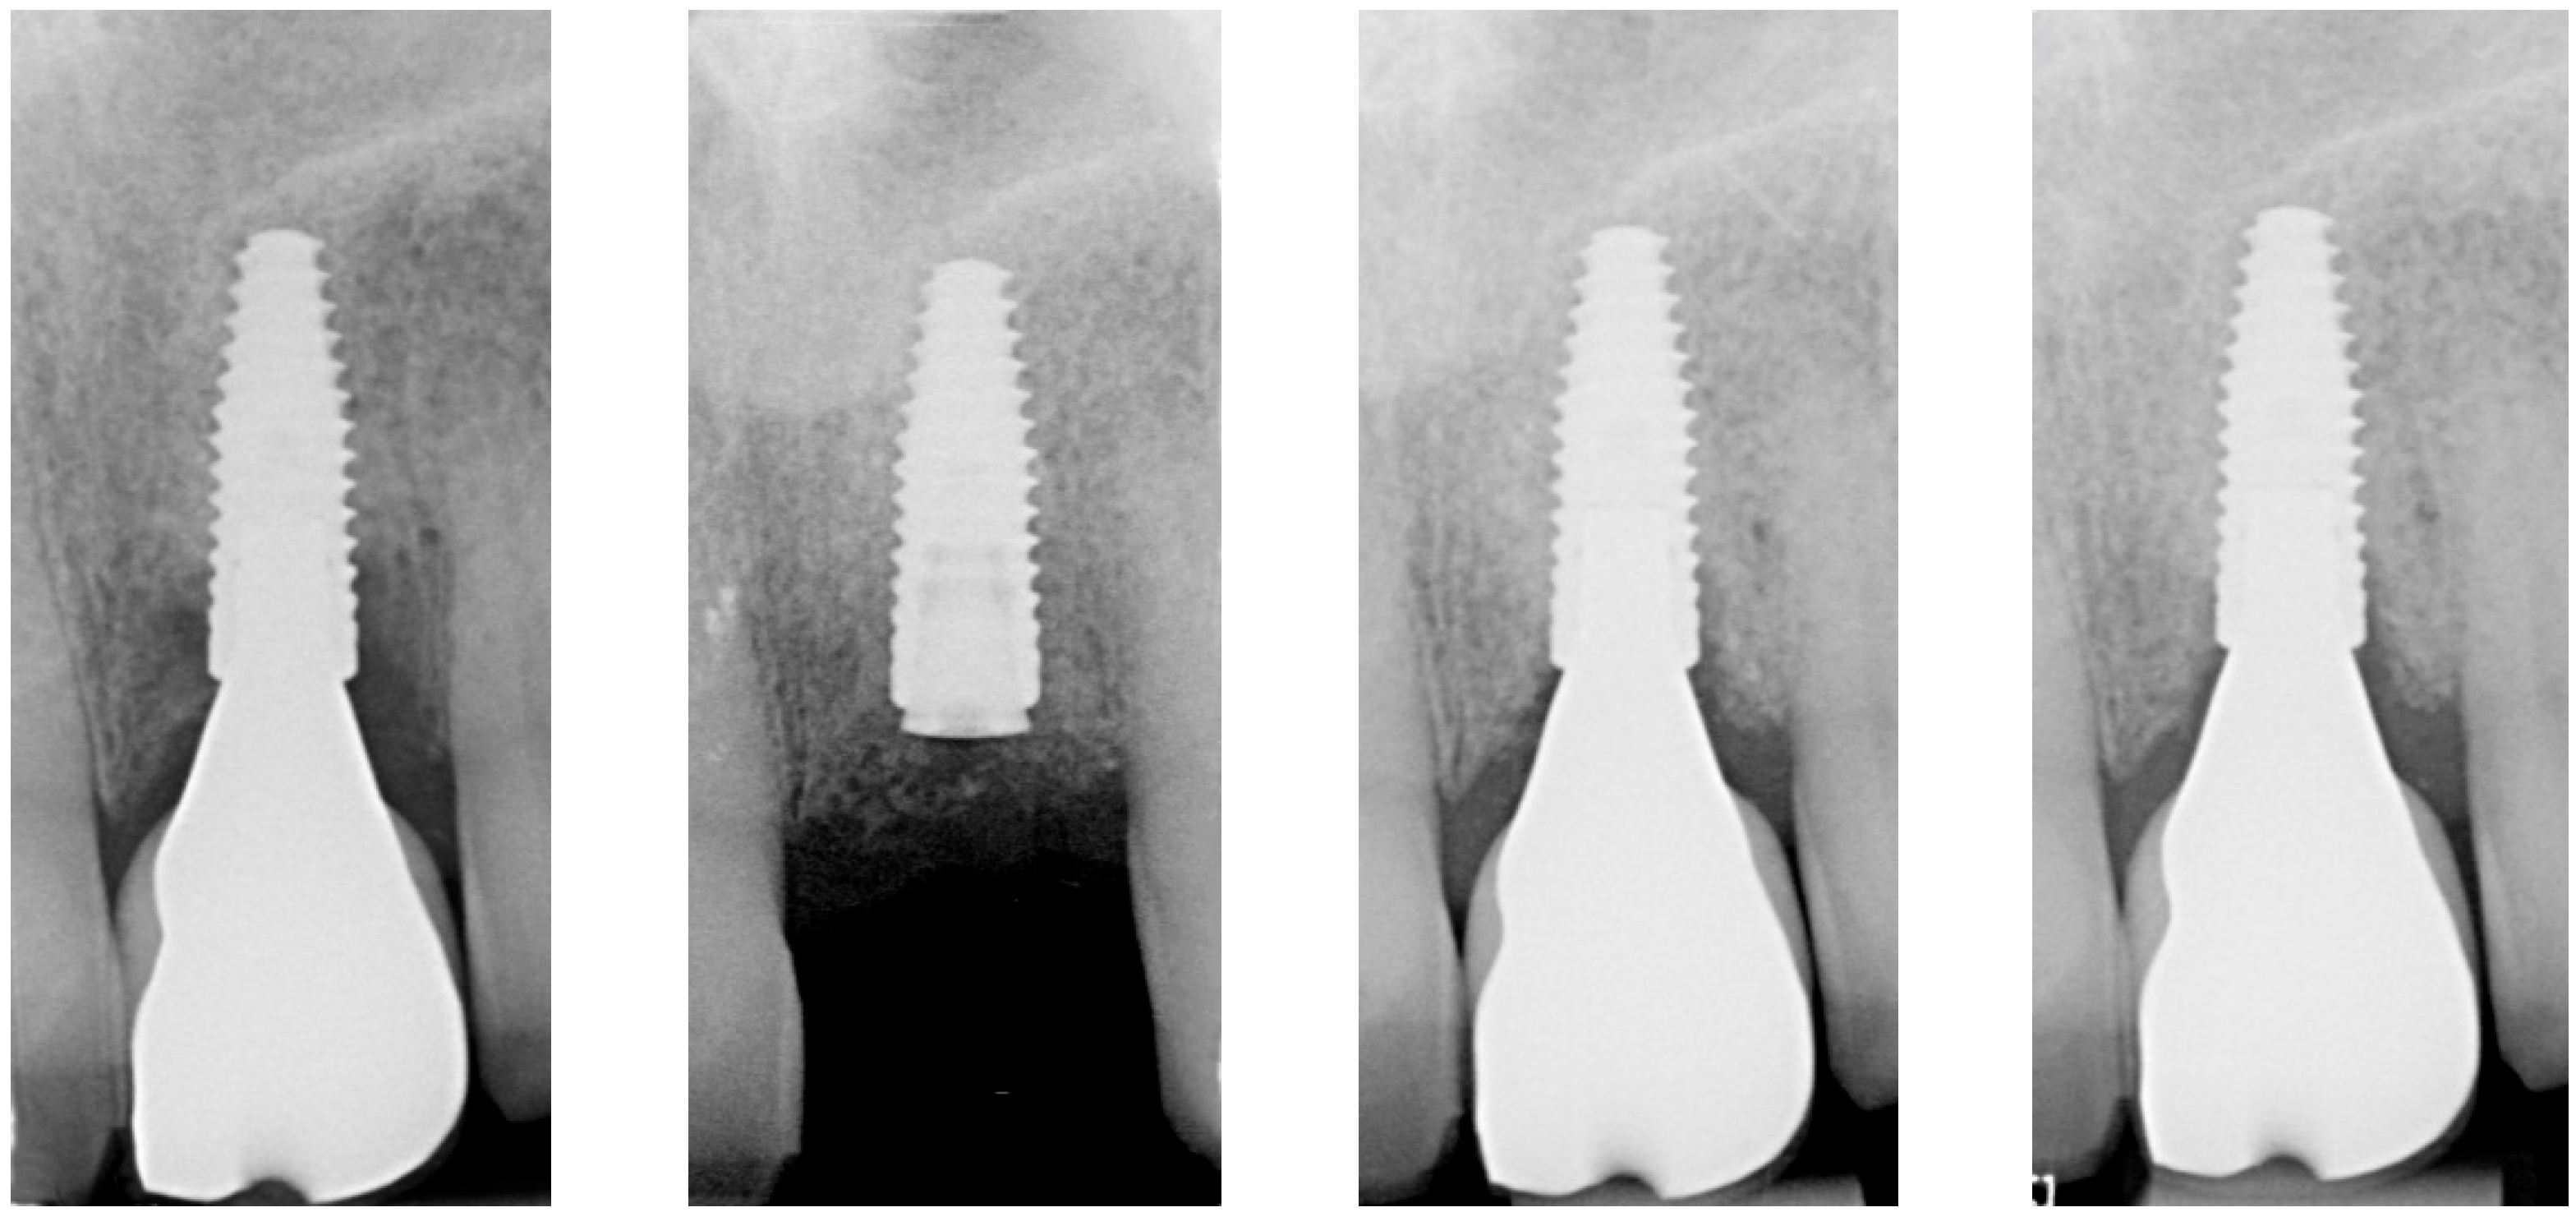

| Radiographic bone level at Tpre mesial (mm) | 5.6 | 3.8 | 1.7 |

| Radiographic bone level at Tpre distal (mm) | 7.6 | 4.2 | 3.2 |

| Radiographic bone level at T2 mesial (mm) | 0.4 | 3.5 | 0.0 |

| Radiographic bone level at T2 distal (mm) | 1.8 | 3.9 | 0.0 |

| Radiographic bone level at T6 mesial (mm) | 2.8 | 3.4 | 1.1 |

| Radiographic bone level at T6 distal (mm) | 3.5 | 0.7 | 2.5 |

| Radiographic bone level at T12 mesial (mm) | 2.3 | 2.5 | 1.7 |

| Radiographic bone level at T12 distal (mm) | 3.5 | 1.5 | 2.5 |